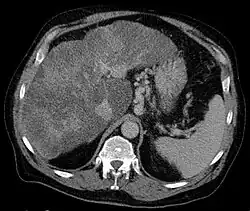

Pomocniczo stosuje się badanie radiologiczne dwukontrastowe, w którym stwierdza się obecność pogrubiałych, krętych, płatowatych fałdów żołądkowych lub okrągły ubytek wypełnienia. W tomografii komputerowej lub rezonansie magnetycznym widoczne są powiększone dobrze odgraniczone okrągłe lub rurowate struktury w dnie żołądka, które mogą dalej przedłużać się w żyły[13][18].